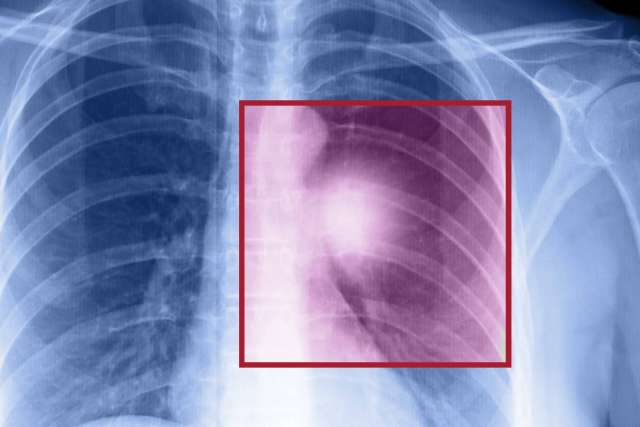

Chest X-ray showing ribcage and lungs with a highlighted square area in red, indicating an abnormality or region of interest.